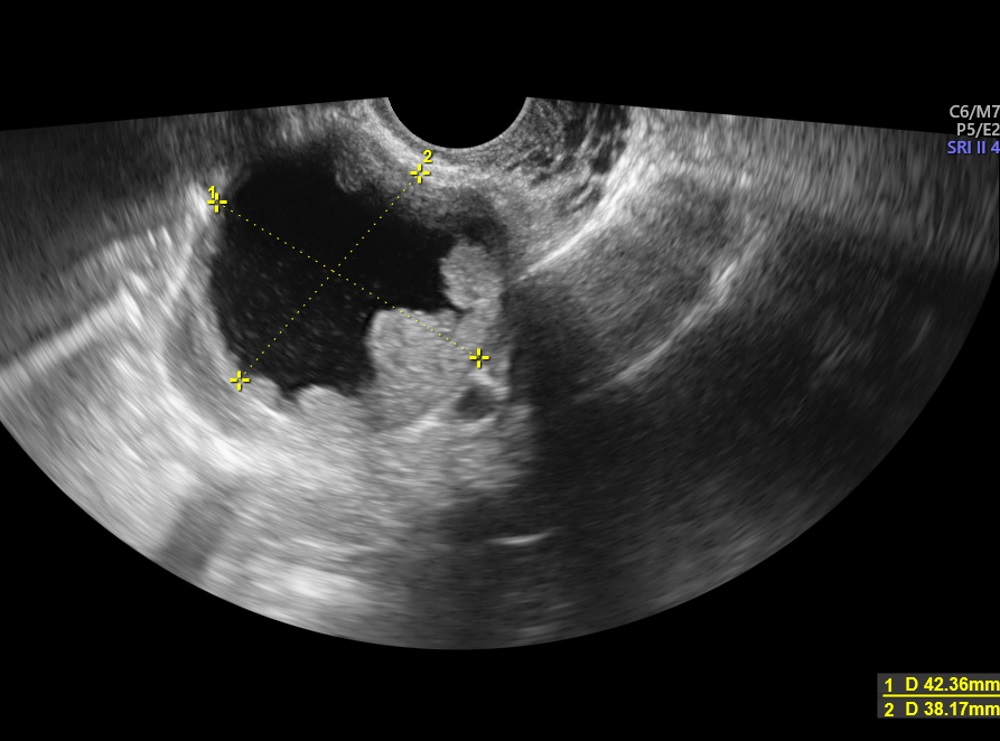

Yumurtalık kisti tedavi edilmezse ne olur. Bu kistler genellikle bulgu vermezler ve tedavi dahi gerektirmezler. Geç kalınır ise üreme sağlığını ciddi olarak etkileyebilir. Yumurtalık için kan akımı kesilir ve tedavi edilmezse yumurtalık dokusuna zarar verebilir veya ölüme neden olabilir. Yumurtalık içinden çikolata kisti tamamen temizlenemediğinde yumurtalıkların alınması gündeme gelebilir.

Kasık ağrılarına yol açabilir. Hemen hemen her kadında hayatının bir döneminde yumurtalıklarında kist saptanabilir. öte yandan boğulma sonucunda yumurtalık dokusunun da dolaşımı bozulduğundan yumurtalık dokusu işlevlerini kalıcı olarak kaybedebilir. Yumurtalık kistleri büyüdükçe içlerindeki sıvının basıncı da artar.